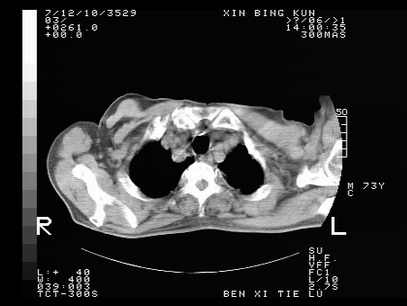

标题: CT10820:男,73岁,病史肺TB,现病史肺炎,直肠CA术后 [打印本页]

标题: CT10820:男,73岁,病史肺TB,现病史肺炎,直肠CA术后

1.两肺结核.2.两肺多发转移瘤.3右侧少量胸腔积液4.主动脉钙化.

1两肺结核2右侧胸腔积液3主动脉硬化

左肺上叶下叶背段,右肺中下叶见多发斑片状、条索状高密度影,兵变周围小结节影形成“树芽”样改变。 左肺上叶舌段近前胸壁处及右肺中叶内侧段见结节影。右侧胸膜腔内见液体密度区。纵隔内未见明确增大淋巴结。考虑左肺上叶舌段近前胸壁处及右肺中叶转移瘤可能性大。两肺继发型肺结核。右侧胸腔积液。

1.两肺结核.2.两肺多发转移瘤.3右侧少量胸腔积液4.主动脉钙化

支持:两肺结核.2.两肺多发转移瘤.3右侧少量胸腔积液4.主动脉钙化.